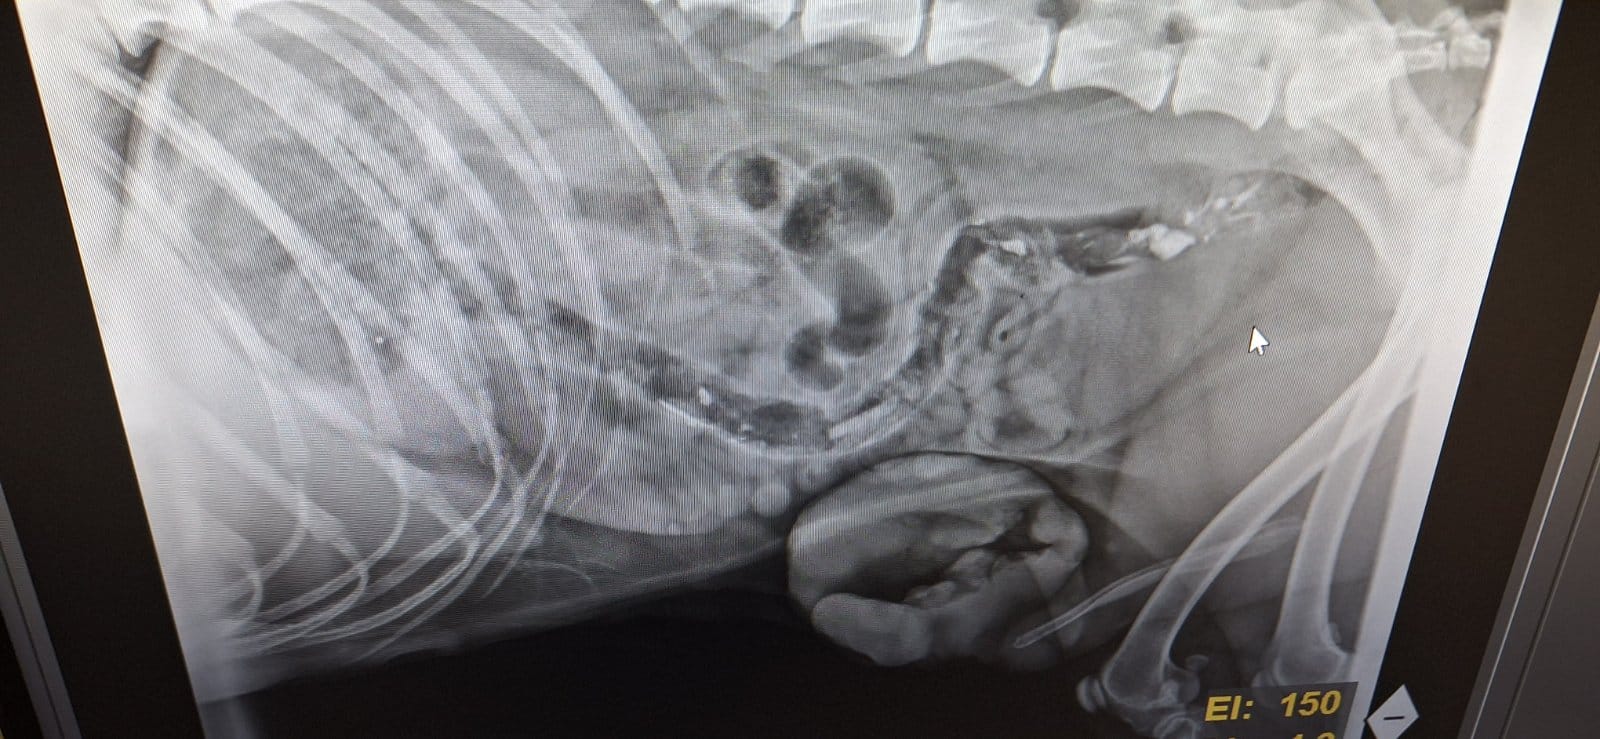

Im September 2025 haben wir Ihnen die kleine Finija vorgestellt: Gerade einmal vier Monate alt, wurde sie in einem erschütternden Zustand gefunden. Beide Hinterbeine waren gebrochen, eine Fortbewegung war für sie nur noch auf den Vorderpfoten möglich. Trotz starker Schmerzen zeigte Finija eine unglaubliche Willenskraft – ein kurzes Video aus…